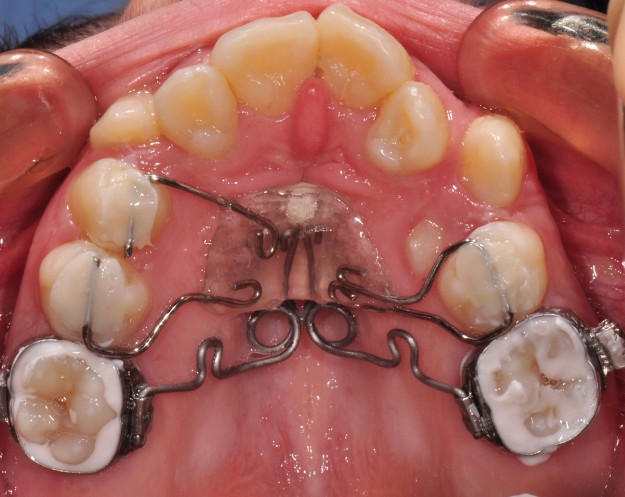

PENDULUM APPLIANCE – PROBLEMS AND POSSIBILITIES IN ITS APPLICATION AT DIFFERENT AGE PERIODS

Статията обсъжда съществували разлика при дистализиране на горни молари, ако пациентите са в различен растежен етап или завършили растежа си, т.е. растящи, млади възрастни и възрастни.